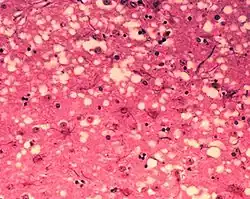

Pasażowalne encefalopatie gąbczaste (ang. Transmissible spongiform encephalopathies, TSE), choroby prionowe – choroby układu nerwowego ludzi i zwierząt spowodowane nagromadzeniem nieprawidłowo pofałdowanych białek zwanych prionami.